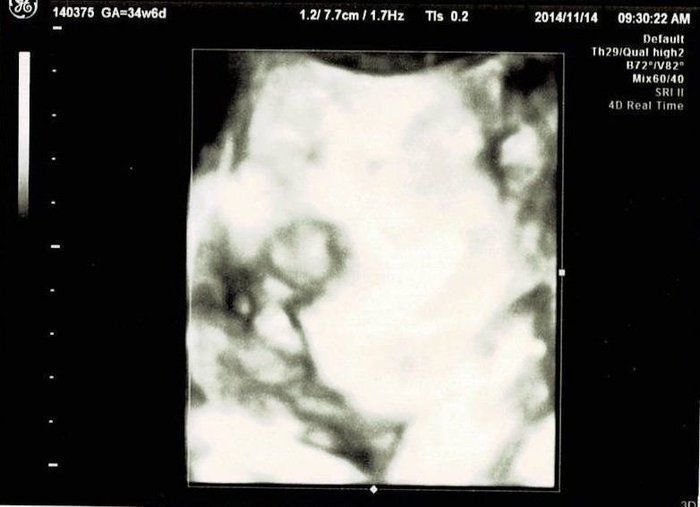

セイコさんの妊娠34週目のエコー写真 里帰り出産のため実家の産院へ移る

こちらの産院だと毎回4Dが撮ってもらえるので、楽しみです。かわいらしい手が結構はっきり写っています。手もほっぺもだいぶぷっくり?体重は2160g、頭の大きさは8.5㎝だそうです。

同じ日ですが、こちらはすごい顔で写っています。この週末は産院で行われた「パパママ育児クラス」に夫婦で参加しました。オムツの替え方、沐浴のさせ方、新生児に関するお話などを聞き、いよいよ本格的に出産の準備。パパたちが率先して挑戦していたのが、ほほえましかったです。